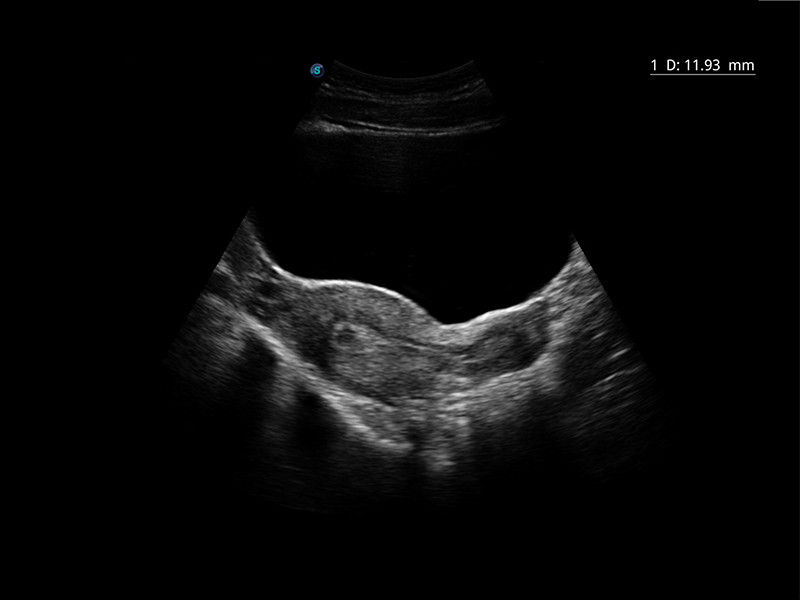

O Auto IMT é usado para determinar o nível de esclerose vascular presente no

paciente, traçando automaticamente a espessura dos vasos carotídeos.